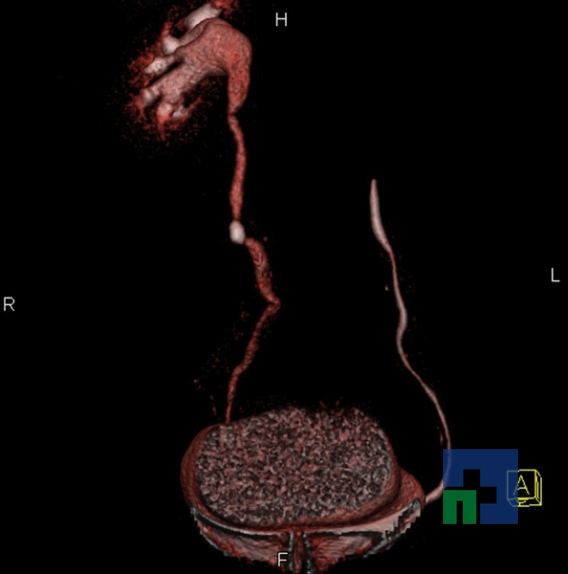

Examinare de rutină cerebrală, nativ și cu substanță de contrast (SDC) pentru diagnosticul:

- Accidentelor vasculare cerebrale ischemice sau hemoragice

- Tumorilor cerebrale